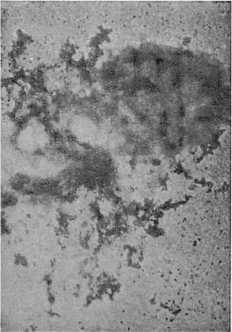

Распадение бактерии дизентерии под действием бактериофагов через 30 минут.

В поле зрения электронного микроскопа ясно видно, как яростно атакуют крошечные бактериофаги этого зловредного гиганта. Быстро устремляются к микробу их хвостатые тельца. Одни из них уже жадно впились в тело бактерии и проникли внутрь. Другие осаждают ее со всех сторон, как стая гончих псов обкладывает большого злого зверя.

Бактериофаги, проникнув внутрь тела микроба, быстро вызывают его распад. Есть предположение, что бактериофаги как бы растворяют тело микроба выделяемыми ими особыми веществами — ферментами.